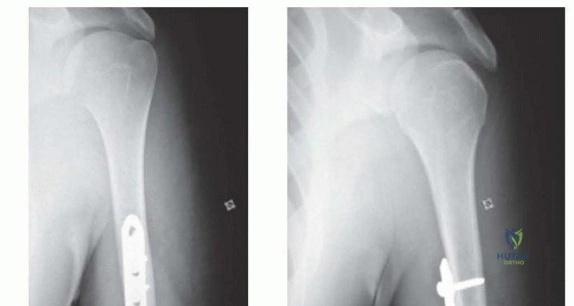

Standard orthogonal radiographs, including an anteroposterior and true lateral of the entire humerus, are mandatory. The imaging must visualize the shoulder and elbow joints to rule out intra-articular extension. Computed tomography is rarely indicated for diaphyseal fractures unless there is suspicion of occult intra-articular extension at the distal humerus.

Digital templating is performed to determine the appropriate plate length. A general biomechanical rule for diaphyseal plating is to achieve a minimum of three to four bicortical screws (six to eight cortices) in both the proximal and distal main fracture fragments. A 4.5 millimeter narrow limited contact dynamic compression plate or locking compression plate is typically selected.

Clinical & Radiographic Imaging